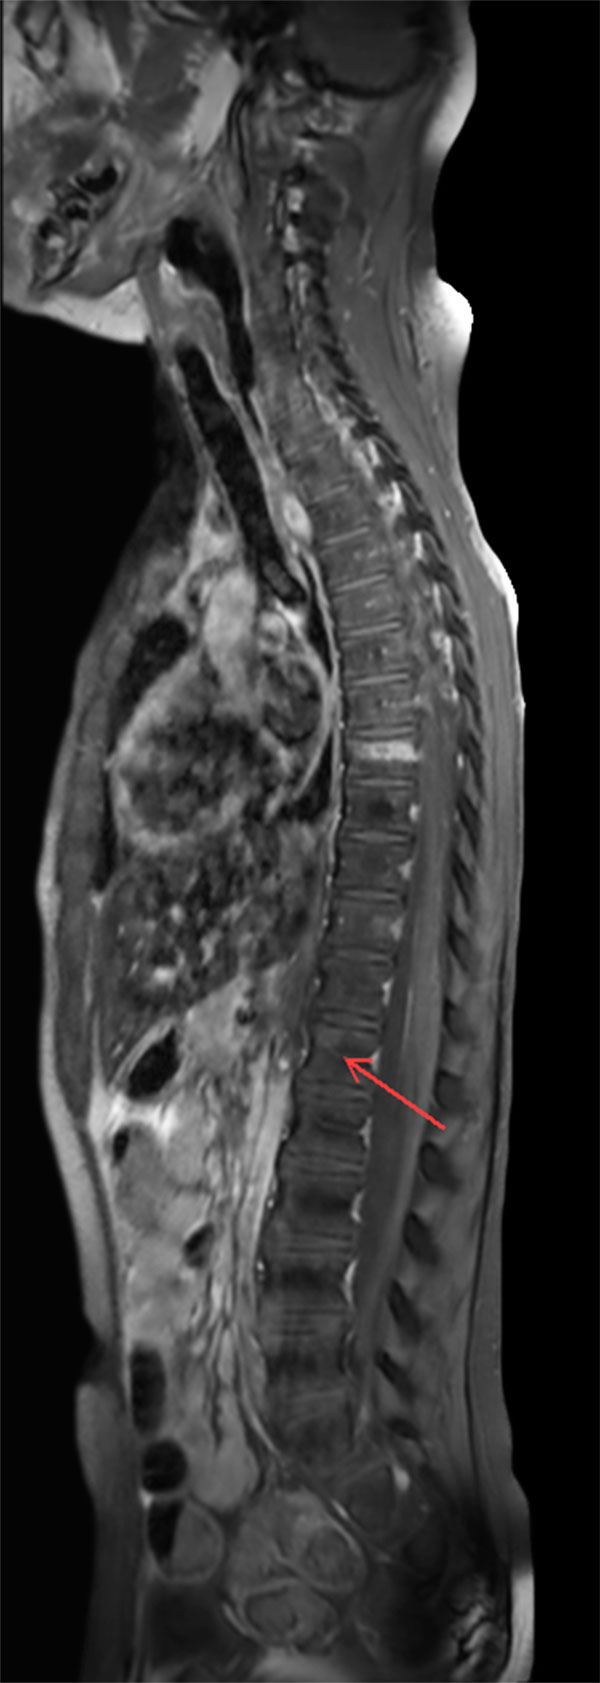

Premium Fat-free Pediatric Spine imaging

Phoenix Children Hospital, USA